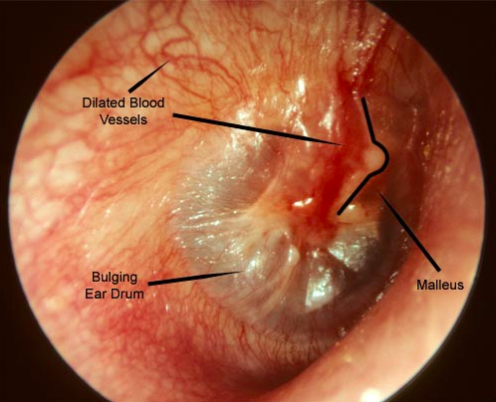

Identifying an ear infection in a child can be challenging, but common symptoms include itchiness, pain when the ear is touched, and in some cases, fluid oozing from the ear. To confirm an ear infection, a doctor will use an otoscope to examine the ear canal. A healthy eardrum appears clear and pinkish-gray, while an infected eardrum will look red and swollen.